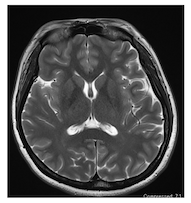

15-36 頭部の T2 強調画像を以下に示す。矢頭(▽)のアーチファクトに関する正しい記述はどれか。3つ選べ。

MRI認定 総集 ランダム